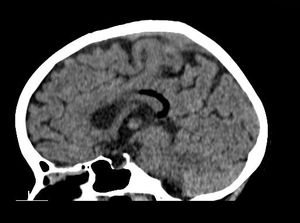

75-year-old male presented with left-sided weakness, headache, and altered sensorium.

48-year-old female presented with complaint of seizures.

30-year-old male presented with nonspecific headaches.